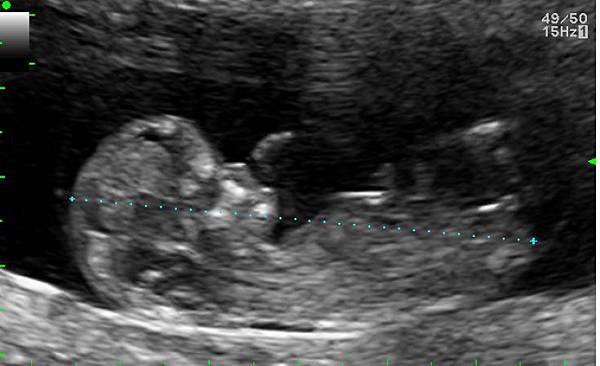

現在,老婆懷孕已三個多月,身體已不適合長時間搭乘飛機。但是,年底又有出國開會的行程,她說,你就自己去啊!以往,自己一個人出差,自己訂機票/飯店、搭車去機場、轉車去飯店、開會,所有的行程,都是自己搞定,即便有助理,還是習慣一個人處理好自己的行程。一些不陌生的瑣碎手續,卻在多次自己一個人的出差中,逐漸感到厭倦。看到特別的東西、吃到好吃的料理,身邊沒人可以立即分享的失落,隨著每次一個人的出差而加重。

小朋友已經3個多月了,希望,他/她將來長大,會喜歡跟著爸爸媽媽一起去自助旅行。